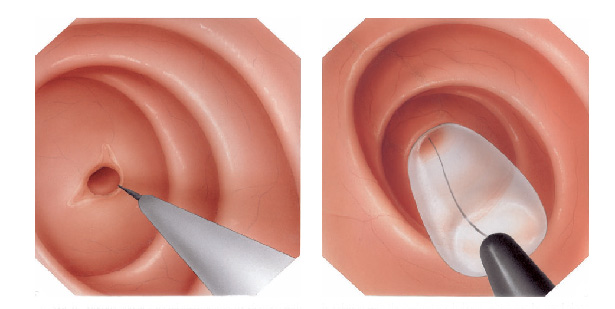

Estenoplastia

Em algumas ocasiões, o estreitamento (estenose) é tão grande que nem os instrumentos de dilatação conseguem passar. Nestes casos e em algumas outras situações, realiza-se o procedimento de estenoplastia. Este consiste na realização de pequenos cortes na região da estenose com auxílio de um estilete que é passado pelo canal de trabalho do endoscópio. Este pequenos cortes ajudam abrir o estreitamento facilitando a passagem dos dilatadores e acelerando o processo do tratamento. Em alguns casos após a realização dos pequenos cortes algumas substâncias, como corticóides, são injetadas na região para prevenir que o estreitamento feche novamente com facilidade.

Estenoplastia

Em algumas ocasiões, o estreitamento (estenose) é tão grande que nem os instrumentos de dilatação conseguem passar. Nestes casos e em algumas outras situações, realiza-se o procedimento de estenoplastia. Este consiste na realização de pequenos cortes na região da estenose com auxílio de um estilete que é passado pelo canal de trabalho do endoscópio. Estes pequenos cortes ajudam abrir o estreitamento facilitando a passagem dos dilatadores e acelerando o processo do tratamento. Em alguns casos após a realização dos pequenos cortes algumas substâncias, como corticóides, são injetadas na região para prevenir que o estreitamento feche novamente com facilidade.

Mucosectomia é o procedimento realizado quando há necessidade de retirada de lesões maiores do trato gastrointestinal.

O exame de Mucosectomia é realizado através de injeção de liquido embaixo da lesão, através de uma agulha específica. Com isso a lesão se destaca das camadas mais profundas do intestino, diminuindo o risco de perfuração.

A retirada da lesão é feita com uma alça de polipectomia e o material é encaminhado para estudo anatomopatológico (no microscópio) da mesma forma que ocorre nas biópsias.

Mucosectomia

Para diminuir este risco, injeta-se com um uma agulha uma solução abaixo do pólipo para que ele levante e fique mais longe da parede do órgão. Após isto passa-se a alça diatérmica e realiza-se o

procedimento de polipectomia.